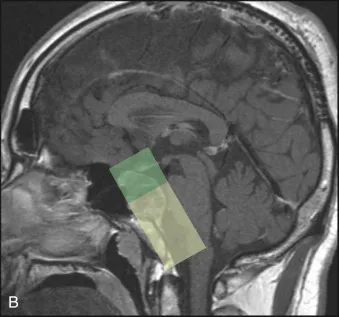

图26.1:斜坡脊索瘤的手术轨迹。(A)内镜经鼻入路手术走廊示意图。经蝶窦入路(绿色)暴露颅底中心的鞍、鞍上和鞍旁区域。经颅内窥镜鼻内入路(黄色)是通过切除下斜坡获得的,在中线提供通往脑干的通路。(B) t1加权磁共振中线矢状面显示经蝶窦入路(上,绿色)和经颅入路(下,黄色)暴露的区域。(C)两名外科医生在内镜经鼻入路中一起工作;在切除肿瘤的过程中,内镜、钻孔和吸痰总是可见的。